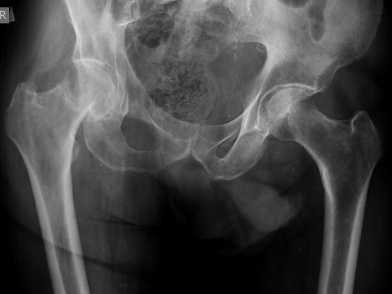

Τα κατάγματα του ισχίου είναι αυτά που συμβαίνουν στο κεντρικό τμήμα του μηριαίου οστού και περιλαμβάνουν τα κατάγματα της κεφαλής του μηριαίου οστού, τα κατάγματα του αυχένα του μηριαίου οστού και τα περιτροχαντήρια κατάγματα. Τα κατάγματα της μηριαίας κεφαλής είναι σπάνια και συνήθως συνοδεύουν το τραυματικό εξάρθρημα του ισχίου. Τα κατάγματα του αυχένα του μηριαίου ή υποκεφαλικά κατάγματα είναι σχετικά συχνά κατάγματα, είναι συνηθισμένα στη μεγάλη ηλικία και μπορούν να συμβούν ακόμα και με μικρή βία (πχ σε μια πτώση από όρθια ή καθιστή θέση). Τα περιτροχαντήρια κατάγματα διακρίνονται σε τρεις κατηγορίες ανάλογα με τη θέση του κατάγματος σε σχέση με τη γραμμή που ενώνει το μείζονα με τον ελάσσονα τροχαντήρα (διατροχαντήριος γραμμή). Αν το κάταγμα συμβαίνει ύπερθεν της διατροχαντηρίου γραμμής ονομάζεται βασεοαυχενικό, αν ακολουθεί τη διατροχαντήριο γραμμή ονομάζεται διατροχαντήριο και αν είναι κάτωθεν της διατροχαντηρίου γραμμής, ονομάζεται υποτροχαντήριο. Τα περιτροχαντήρια κατάγματα συμβαίνουν κι αυτά συνήθως σε μεγάλη ηλικία μετά από κάποια πτώση από την όρθια ή την καθιστή θέση.

Η διάγνωση γίνεται από την κλινική εξέταση σε συνδυασμό με το ιστορικό της κάκωσης και επιβεβαιώνεται με απλή ακτινογραφία. Σε περιπτώσεις που η καταγματική γραμμή δεν φαίνεται καθαρά στην απλή ακτινογραφία, τότε πραγματοποιείται αξονική τομογραφία η οποία απεικονίζει με λεπτομέρεια τα οστά της περιοχής.